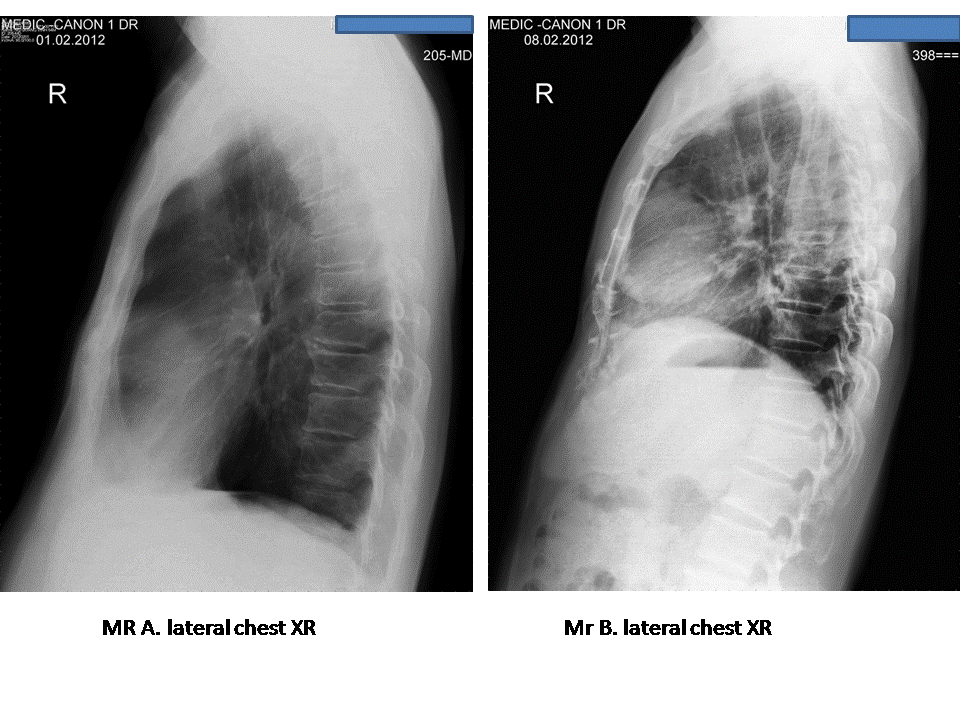

VIETNAMESE MEDIC ULTRASOUND CASE 188 MEDIC RADIOLOGY CASE 5 THYMOMA Thymus Gland Ultrasound Chemical shift mri depicts no decrease in signal. Radiologists play a major role in differentiating normal thymic variants, ectopic thymic tissue, and nonneoplastic thymic conditions such as rebound hyperplasia from neoplastic conditions. Moreover, most patients with thymic tumors are asymptomatic at the time of diagnosis. Since the thymus is anatomically located in the anterior superior mediastinum, where the 50% of. Thymus Gland Ultrasound.